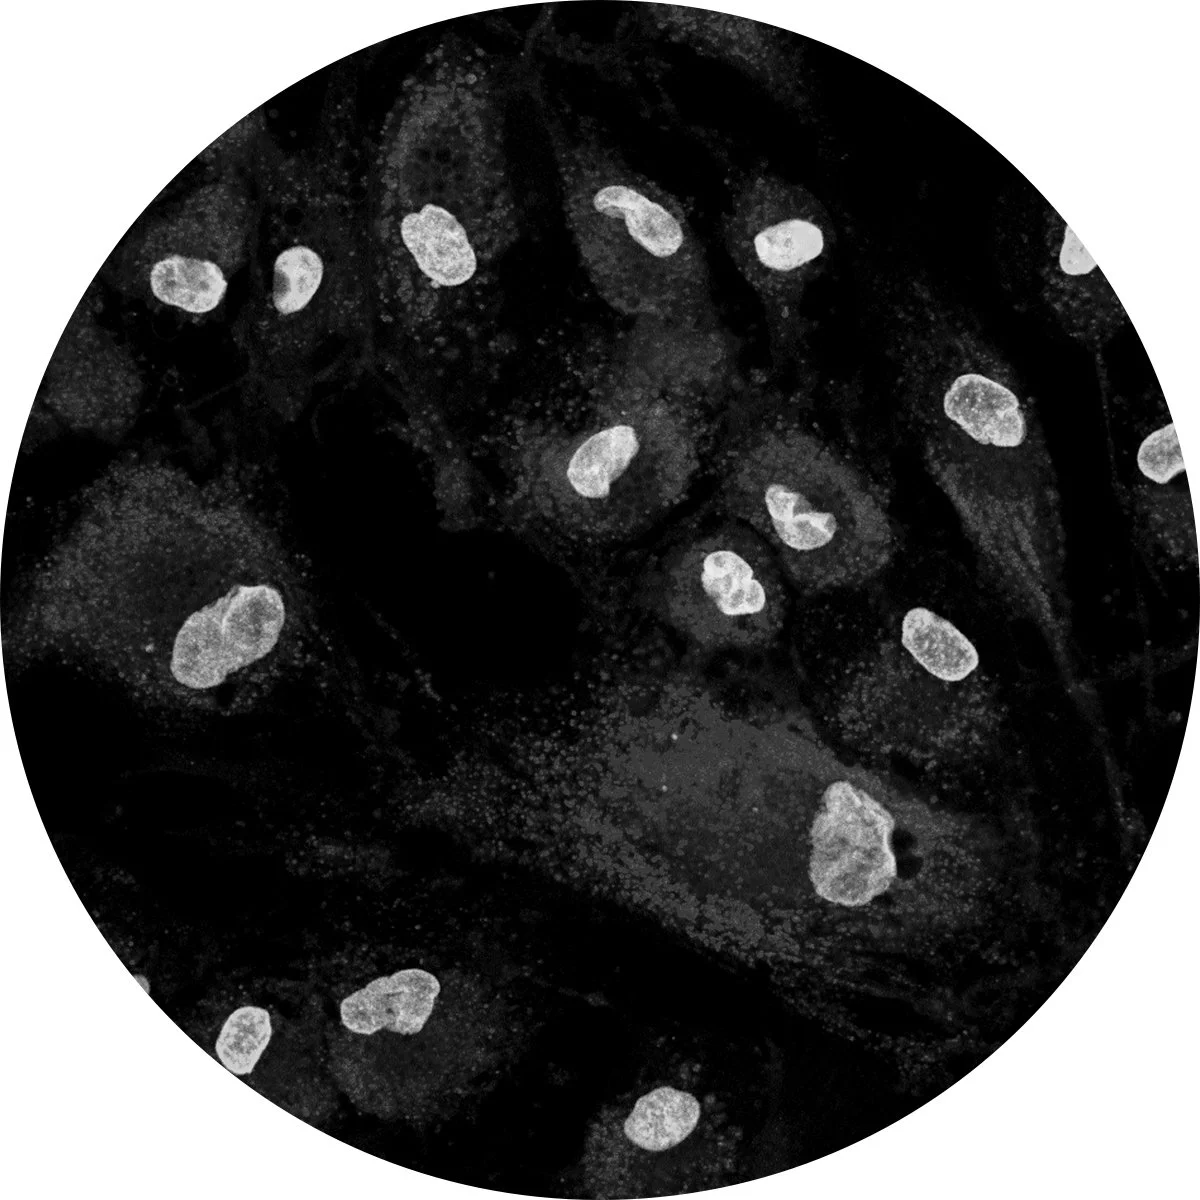

The Bionaut Platform is designed to overcome key challenges of drug delivery into the central nervous system including blood brain barrier, drug diffusion into brain tissue and intra-tumoral pressure, to improve drug efficacy and safety.

Bionauts carry therapeutic payloads to regions of brain that are currently difficult or impossible to access.

Bionauts enable precise drug delivery to treat conditions at the site of disease to enhance drug efficacy while avoiding off-target toxicity